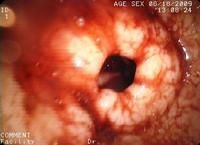

食管炎胃鏡1.脾痹(心痛):以胸悶短氣或發作性心胸疼痛為主,常於勞累後發作,多無胸骨:後燒灼感及吞咽困難。心電圖示ST-T呈缺血性改變。食管滴酸試驗陰性。

3.內鏡及活組織檢查:內鏡下可將食管炎症病變分為5級,

0級為正常黏膜

1級為食管下段有一處或幾處表現為充血或伴有滲出的非融合性病變

2級為融合性病變,但尚未呈環周病變,表現為充血、糜爛和滲出

3級為環周病變,表現為糜爛和滲出

4級呈慢性病變,表現為潰瘍、狹窄、Barrett食管等。